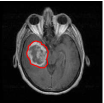

We adopt and suitably customize the shape definition of Srivastava et al. (2011) that is particularly attractive in the current context (see (Joshi et al., 2007a, b), (Srivastava et al., 2011), and (Kurtek et al., 2012) for details). While describing the tools, we concurrently illustrate their usage on the GBM dataset. To get an idea of this problem’s complexity, we display a few examples of tumor contours overlaid on the corresponding T1-weighted post-contrast and T2-weighted FLAIR MRI slices in Figure 2. The tumor shapes are heterogeneous and at first glance, it is difficult to ascertain any relationship between tumor shapes and survival times. To obtain insight into possible relationships between tumor shapes and outcomes, more sophisticated approaches are required.